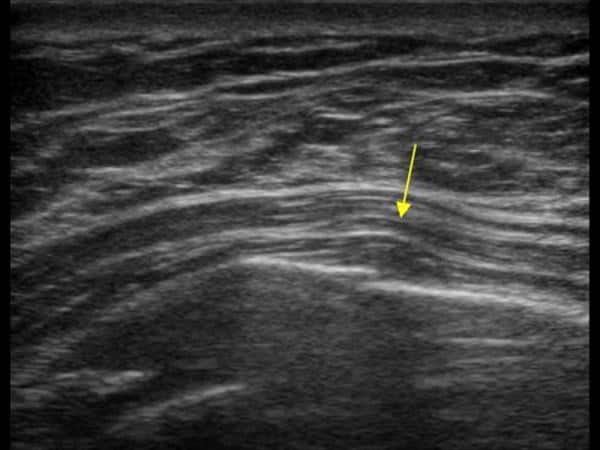

Gãy xương sườn

Gãy xương sườn - Ảnh 2

» Thông tin: Nữ giới – 52 tuổi.

» Lâm sàng: Chấn thương ngực.